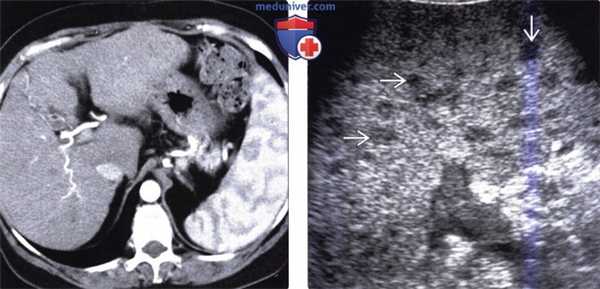

(Слева) На корональной КТ с контрастным усилением определяется умеренно выраженное увеличение селезенки с наличием множественных гиподенсных узлов в ее паренхиме. Позднее у этого же пациента была выявлена внутригрудная лимфаденопатия; при биопсии селезенки подтвердился саркоидоз.

(Справа) На аксиальной Т2 ВИ МР томограмме определяется выраженное снижение интенсивности сигнала от печени, селезенки и костного мозга у пациента с гемосидерозом, обусловленным множественными переливаниями крови.

(Слева) На аксиальной КТ с контрастом визуализируется в значительной степени увеличенная селезенка с множественными нечеткими гиподенсными очагами, разбросанными по всей паренхиме. Эти изменения обусловлены лимфомой, также имеет место генерализованная лимфаденопатия.

(Справа) На аксиальной КТ с контрастным усилением у пациента с неходжкинекой лимфомой определяется спленомегалия и выраженная лимфаденопатия. Аналогично могут проявляться и другие (доброкачественные) процессы, например, саркоидоз.

(Слева) На аксиальной КТ в артериальную фазу контрастного усиления у пациента с циррозом (печени) и портальной гипертензией определяются изменения внешнего вида селезенки в виде «муарового узора», обусловленные неравномерным контрастным усилением, которые исчезают в портально-венозную фазу. Это вариант нормы часто более выражен у пациентов с циррозом печени и портальной гипертензией.

(Справа) На сонограмме у пациента с гранулематозной микобактериальной авиум-внутриклеточной инфекцией визуализируется увеличенная селезенка с множественными гипоэхогенными очагами. На УЗИ гранулематозные абсцессы выглядят как четко отграниченные гипоэхогенные образования (обычно в сочетании со спленомегалией).